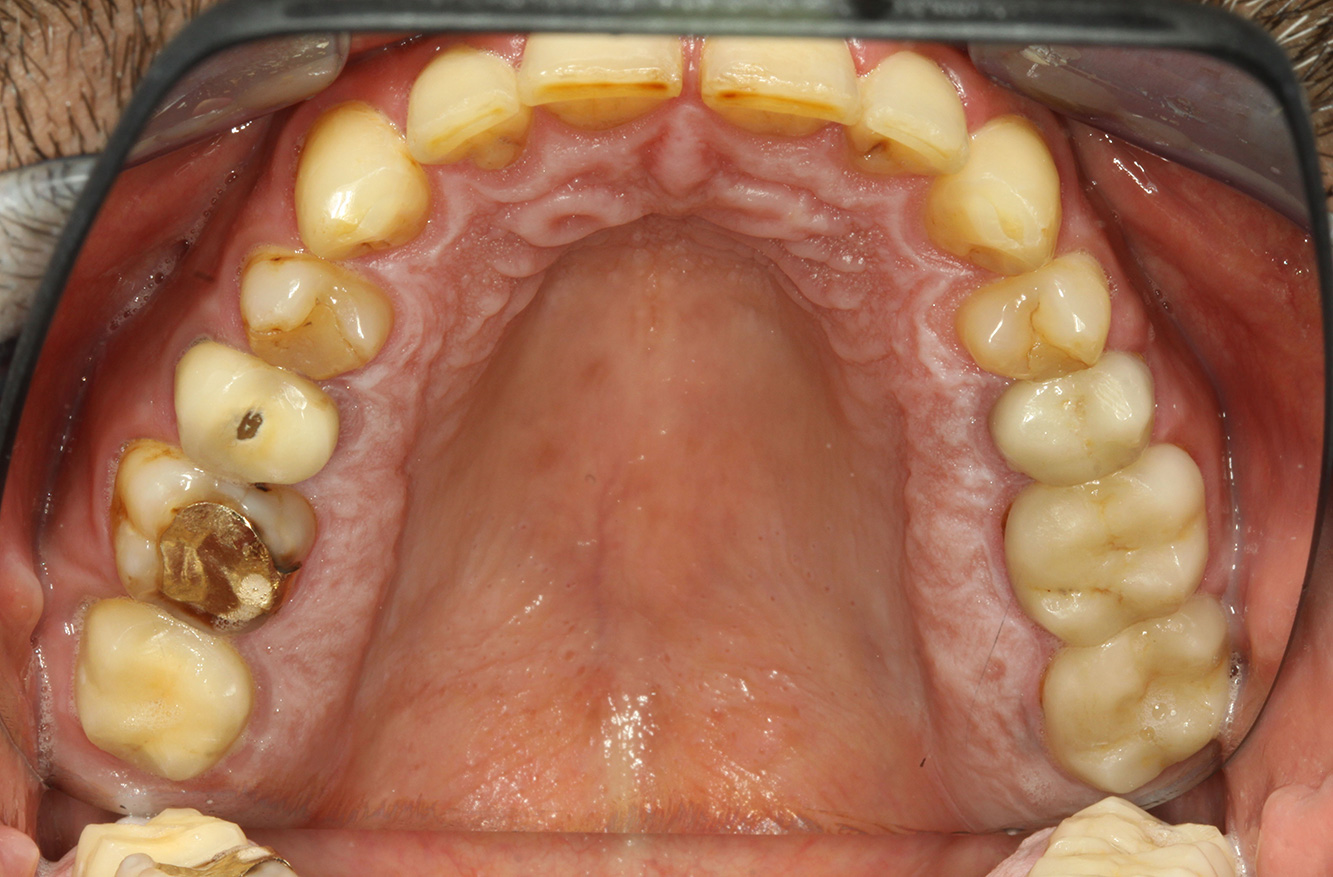

The endocarditis patient with active caries lesions*

The patient is 39 years old and has previously undergone aortic valve replacement due to valve failure and endocarditis. ASS 100 is taken regularly as an anticoagulant. In terms of lifestyle, the patient’s diet is classified as caries-promoting due to the regular consumption of sugary foods and the fact that six to seven meals are consumed daily. The patient’s oral health indicates a moderate risk of caries, with active lesions. The risk of periodontitis is low, but gingivitis is present. The following recommendations are made for prophylactic treatment.

No specific instrument recommendations can be determined for the prophylaxis session. Targeted application of air and rotary polishing can be used to gently reduce plaque and stains on the restoration edges, and to reduce recolonization niches for cariogenic bacteria (19).

Fluoridation is recommended to further support the prevention of caries, and especially to prevent new formation around thethe restoration edges, and to seal the root surfaces. Both of these measures can reduce the teeth’s sensitivity to temperature.

Due to the active caries lesions and the associated risk of progression, a shortened recall interval of three to four months is recommended.